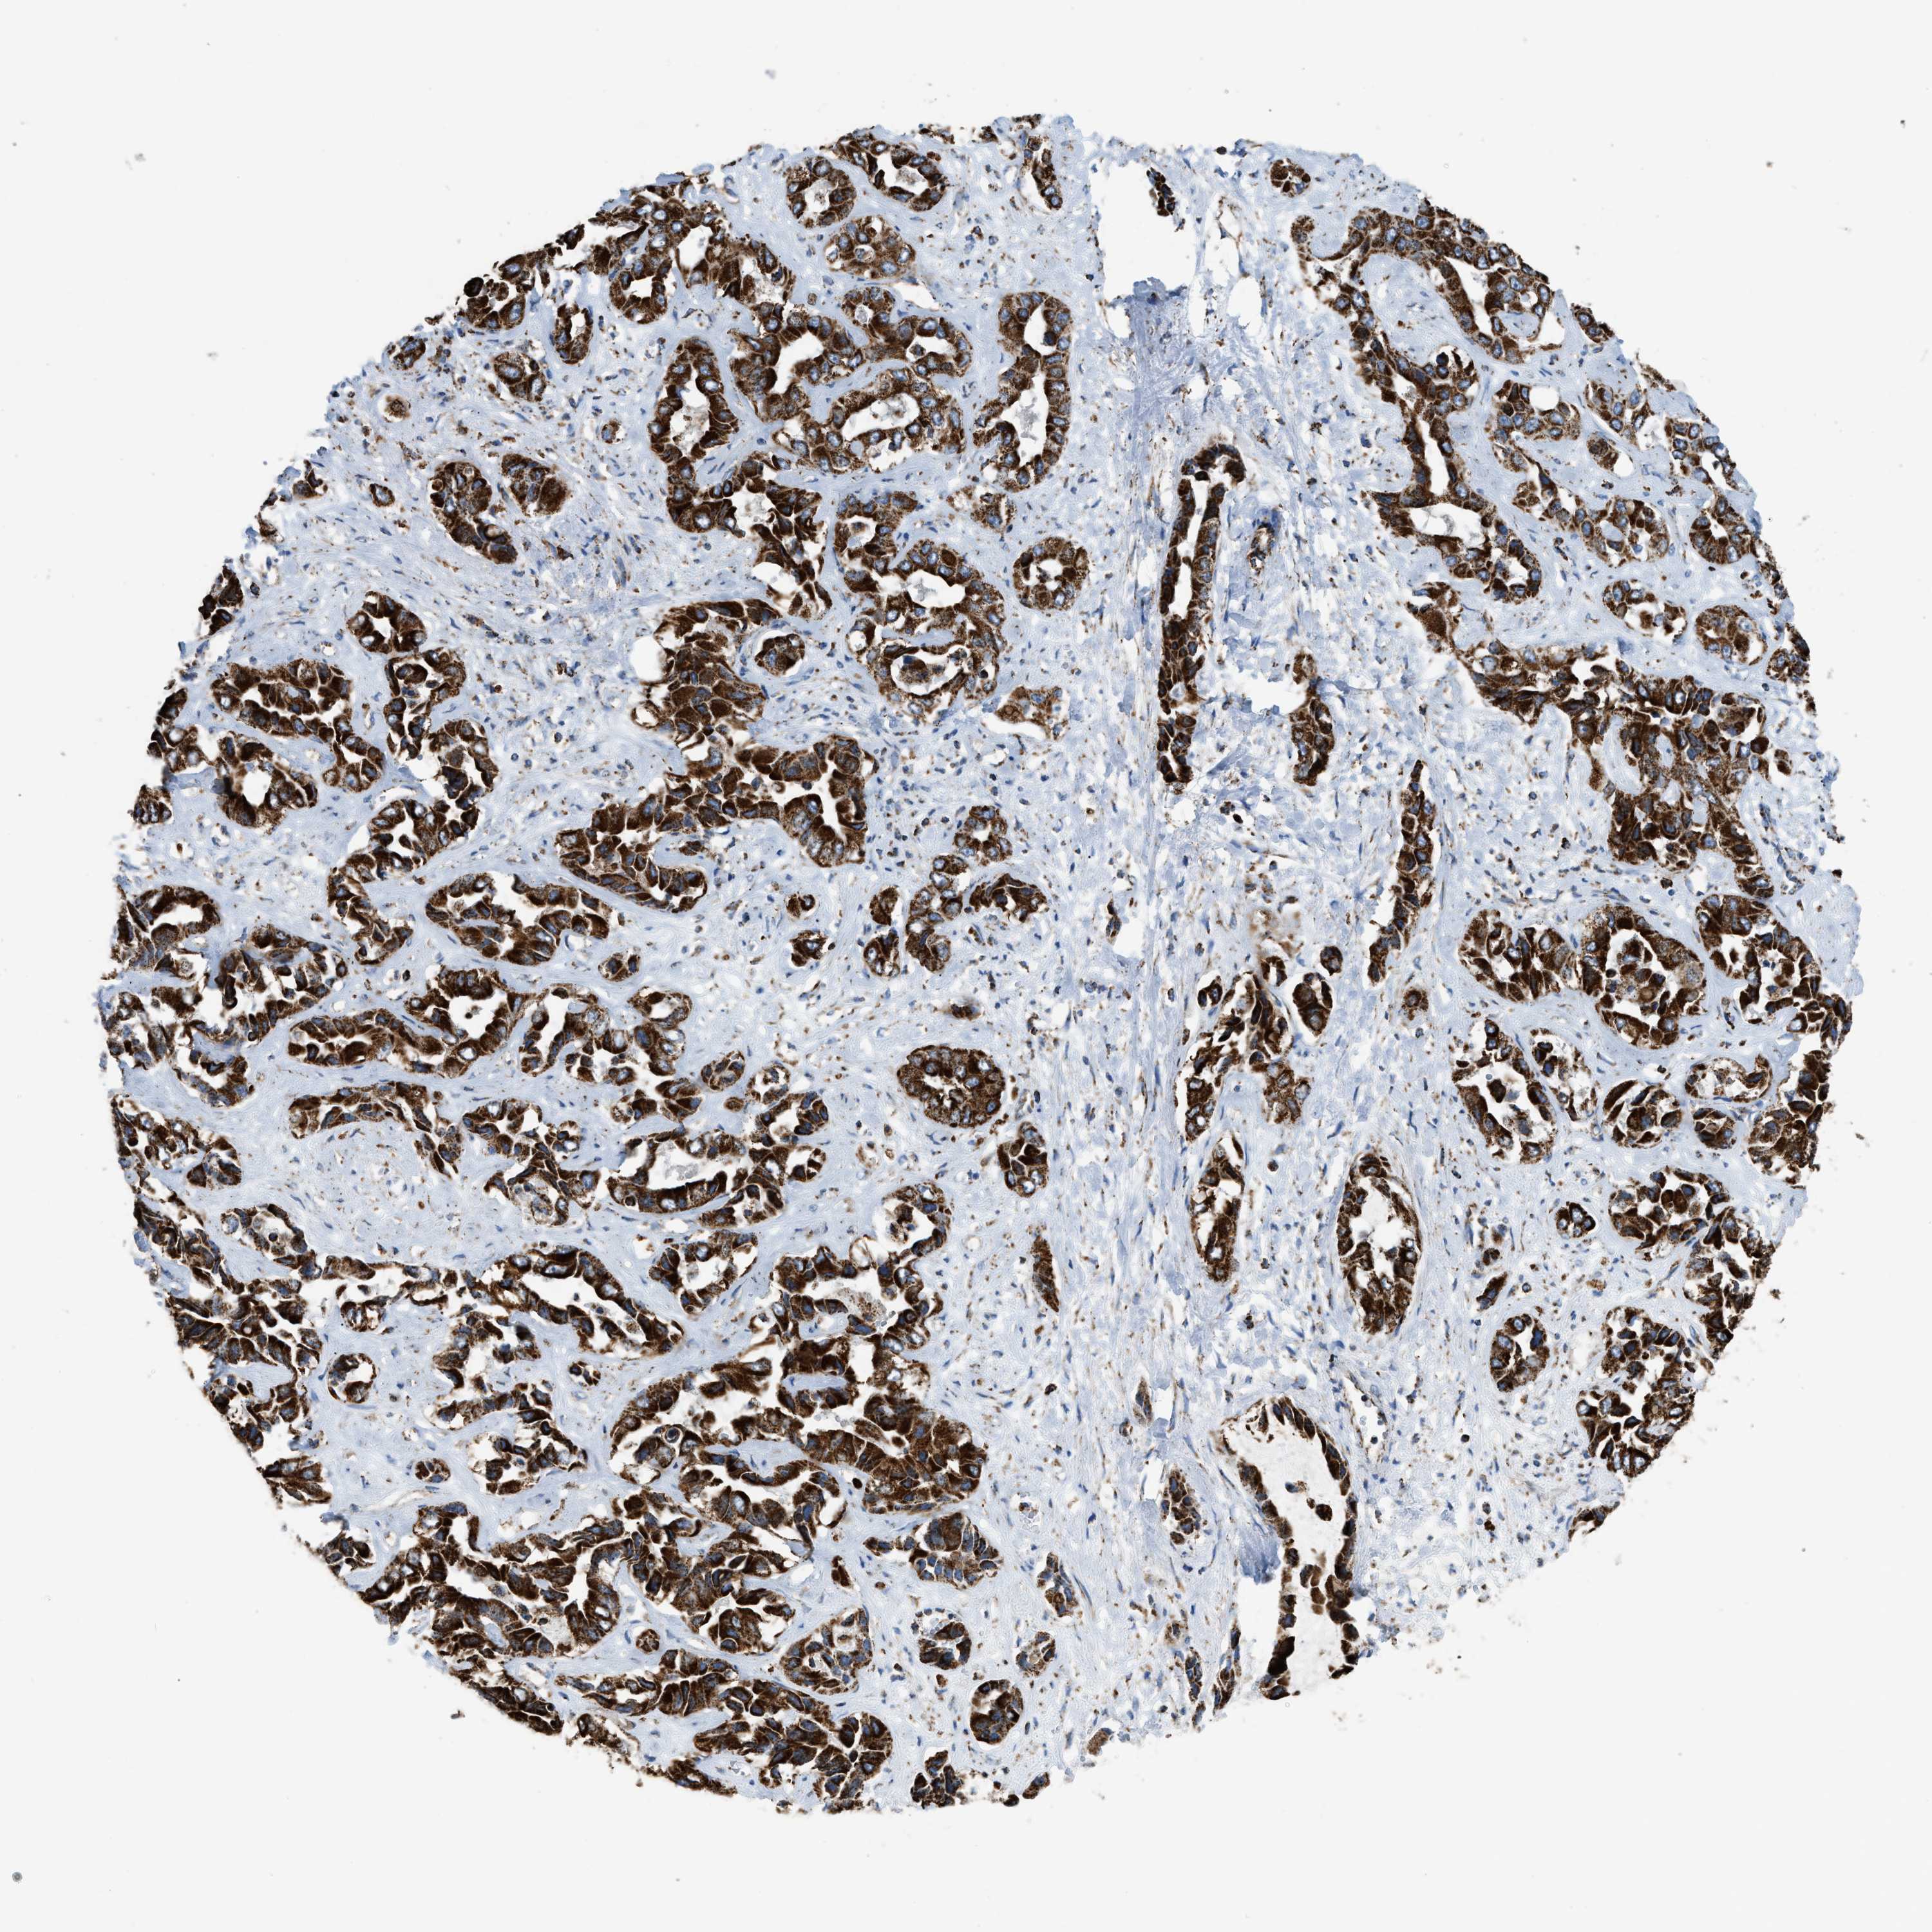

LIVER CANCER - Protein expressioni

A mouse-over function shows sample information and annotation data. Click on an image to view it in a full screen mode. Samples can be filtered based on level of antibody staining by selecting one or several of the following categories: high, medium, low and not detected. The assay and annotation is described here.

Note that samples used for immunohistochemistry by the Human Protein Atlas do not correspond to samples in the TCGA dataset.

Antibody stainingi

Antibody staining in the annotated cell types in the current human tissue is reported as not detected, low, medium, or high, based on conventional immunohistochemistry profiling in selected tissues. This score is based on the combination of the staining intensity and fraction of stained cells.

Each image is clickable and will lead to virtual microscopy that enables deeper exploration of all samples and also displays staining intensity scores, fraction scores and subcellular localization as well as patient and tissue information for each sample.

Antibody HPA018910

Antibody HPA018921

Antibody HPA018923

Staining

High

Medium

Low

Not detected

Intensity

Strong

Moderate

Weak

Negative

Quantity

>75%

75%-25%

<25%

None

Location

Nuclear

Cytoplasmic/membranous

Cytoplasmic/membranous,nuclear

Cholangiocarcinoma

Carcinoma, Hepatocellular, NOS